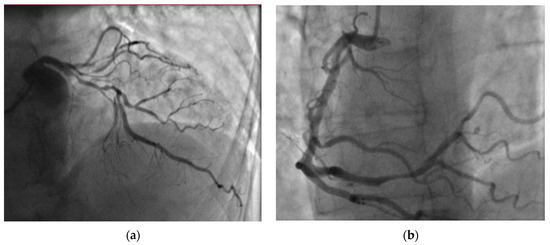

Following the exclusion of PE, coronary artery angiography (CA) was performed to investigate the possibility of external compression of the left coronary ostium due to a dilated pulmonary trunk. However, CA revealed a two-vessel CAD with the following CA stenoses: S3—75, S4—100, S6—75, S7—75, S9—90%) (Figure 4). After receiving a loading dose of two antiplatelet agents, the patient underwent a successful percutaneous coronary intervention (PCI) on segments S6, S7, and S8 with 2 drug-eluting stents (40- and 24-mm length).

Figure 4. Coronary angiography revealed two-vessel coronary artery disease: (a) significant left anterior descending artery stenoses and (b) right coronary artery distal stenoses.